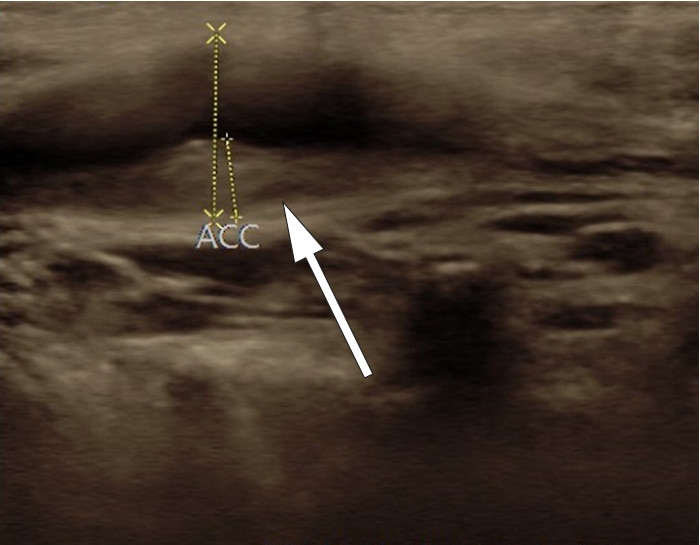

Ved klinisk undersøkelse fant man palpasjonsømhet under høyre bifurkatur. Det var ingen nevrologiske utfall. CT angio av halskar viste intet sikkert patologisk. Derfor ble det gjort ny ultralyd av halskarene, og man fant normalt kaliber av aktuelle carotisbifurkatur. På stillbilder var det vanskelig å se noe galt, men med løpende avbildning så man en isodens fortykkelse i åreveggen som ble oppfattet som en disseksjon. Forandringen var forsvunnet ved ultralydkontroll fire måneder senere, noe som bekreftet diagnosen. MR angio tatt seks uker etter symptomstart viste normale halskar.

Hos denne pasienten var vegghematomet isodenst og vanskelig å se på stillbilder, særlig ved den siste ultralydundersøkelsen (bildet til høyre). Ved den initiale undersøkelsen fremsto det noe tydeligere (bildet til venstre). På videoene kan man se disseksjonen som en veggfortykkelse som beveger seg sammen med karet og ikke med det underliggende vevet.